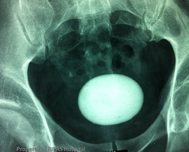

Bladder Stone